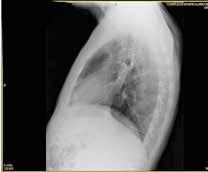

Se revisaron las pruebas solicitadas en Urgencias. En la analítica se en contró una hemoglobina (Hb) de 14 g/dl, un volumen corpuscular medio (VCM) elevado (106μ³) compatible con su historia de alcoholismo o con un déficit de ácido fólico o vitamina B12, una discreta elevación de la proteina C reactiva (13,2 mg/dl) sin elevación de otros reactantes de fase aguda y unas enzimas hepáticas dentro de la normalidad, con la aspartato transfe rasa ligeramente elevada 39 U/L (rango de normalidad: 5-34). Los tóxicos en orina fueron negativos, así como la etanolemia. La radiografía (rx) de tórax mostraba una condensación en el lóbulo superior izquierdo en posi ble relación con la infección tuberculosa diagnosticada en 2011 (Figura 1). La TC -a pesar de no mostrar signos de patología aguda intracraneal, ni masas ni signos de sangrado- sí que mostraba atrofia cerebral con surcos muy marcados, hallazgo no concordante con la edad de nuestro paciente (Imagen 2).

Figura 1. Radiografía de tórax en bipedestación AP y Lat.

Lesiones residuales/cicatriciales en campo superior izquierda, con aumento de densidad de parénquima, bronquictasias y pérdida de volumen, en relación con antecedente de TBC. Parénquima pulmonar derecho aceptablemente ventilado. Siluesta cardiovascular normal.